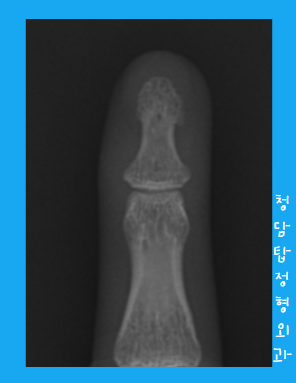

진짜 마지막으로 엑스레이 다시 찍어볼게요!

이제 진짜 깨끗하게 제거가 됐습니다.